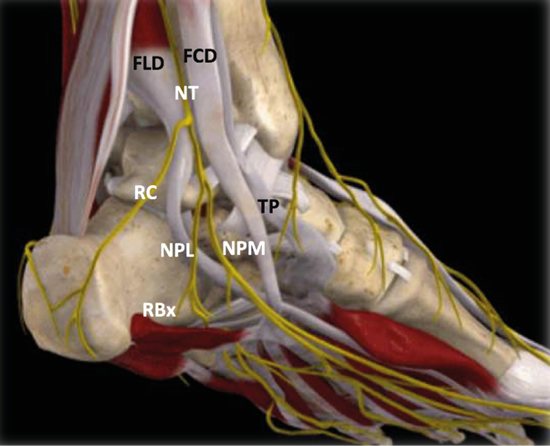

Figura 3. Túnel tibiotalocalcáneo. El nervio tibial (NT) se divide en la rama calcánea (RC), el nervio plantar medial (NPM) y el nervio plantar lateral (NPL) del que se escinde la rama de Baxter (RBx). Las estructuras musculotendinosas tibial posterior (TP), flexor largo del primer dedo (FLD) y flexor largo de los dedos (FCD) acompañan al nervio tibial en su recorrido por la cara medial del tobillo y el pie. Imagen modificada de la App Ankle & Foot Pro III.

Figura 5. Túnel tibiotalocalcáneo. La porción proximal o túnel tibiotalar superior en azul. Estructuras nerviosas: nervio tibial (NT), rama calcánea (RC), nervio plantar lateral (NPL), nervio plantar medial (NPM), rama de Baxter (RBx). Estructuras musculotendinosas: tibial posterior (TP), flexor largo del primer dedo (FLD) y flexor largo de los dedos (FCD). Imagen modificada de la App Ankle & Foot Pro III.